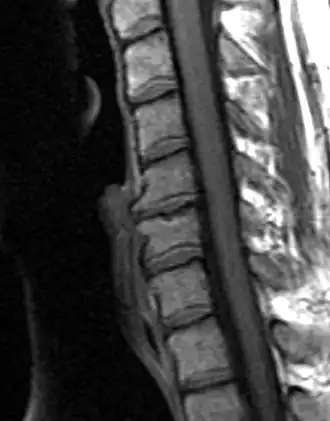

![]() Дегенеративно-дистрофическое заболевание диска, C5-C6 с остеофитами | |

Типичными рентгенографическими данными ДДЗД являются черные диски, сужение дискового пространства, вакуумные диски, склероз конечной пластинки и образование остеофитов[2][3].

Диагностика дегенеративно-дистрофического заболевания диска обычно состоит из анализа индивидуальной истории болезни пациента, физикального исследования, предназначенного для выявления мышечной слабости, болевого синдрома, определения объёма движения, и МРТ-сканирования для подтверждения диагноза и исключения других причин.